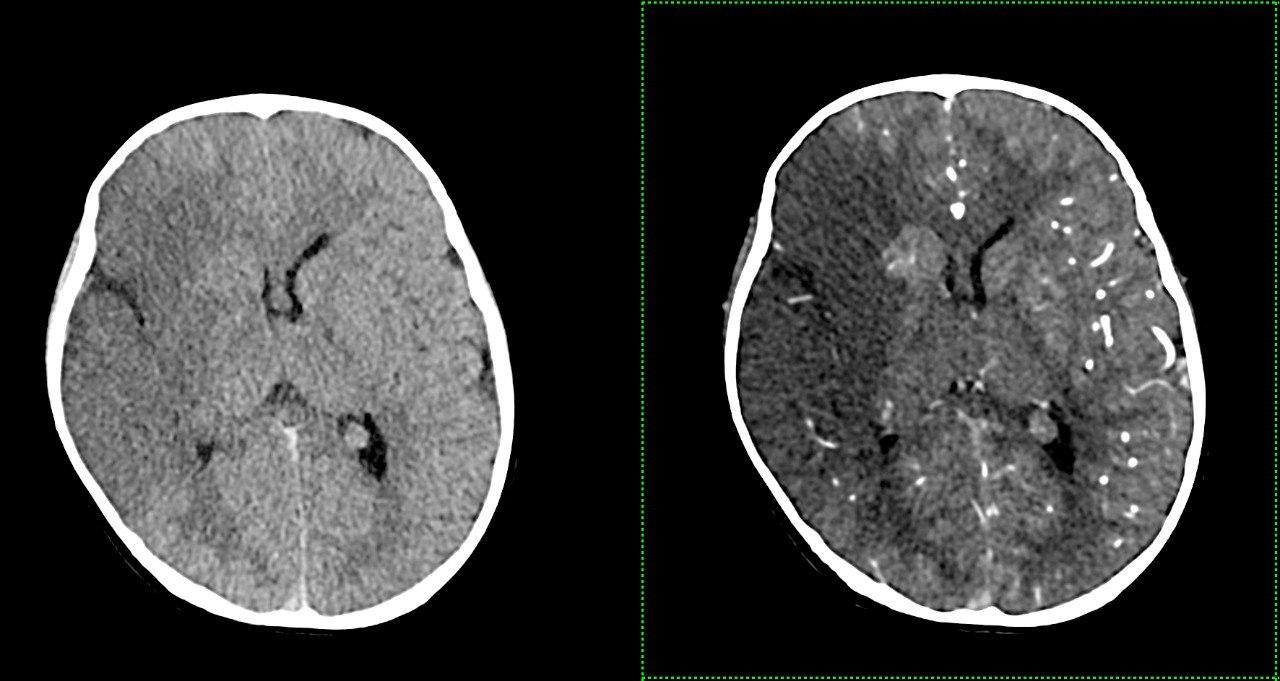

- КТ: створює детальні зображення кісток та м’яких тканин у вигляді “зрізів”. Дозволяє виявити навіть найменші зміни.

Комп’ютерна томографія: Надає детальні зображення внутрішніх органів та тканин, допомагає виявити пухлини, запалення та травми.

Магнітно-резонансна томографія: Найточніший метод для дослідження мозку, хребта, суглобів та м’яких тканин. Абсолютно безпечний тому також підходить для візуалізації вагітних, дослідженні плоду. Разом КТ та МРТ показані для виявлення вроджених аномалій розвитку/патології центральної нервової, скелетно-м’язової, травної, дихальної, сечовидільної системи, статевої сфери Також показані пацієнтам та потенційним донорам при підготовці до трансплантації,

- Комп’ютерна томографія: Siemens SOMATOM X.cite (128 зрізів, мах. 364 реконструйовані зрізи)